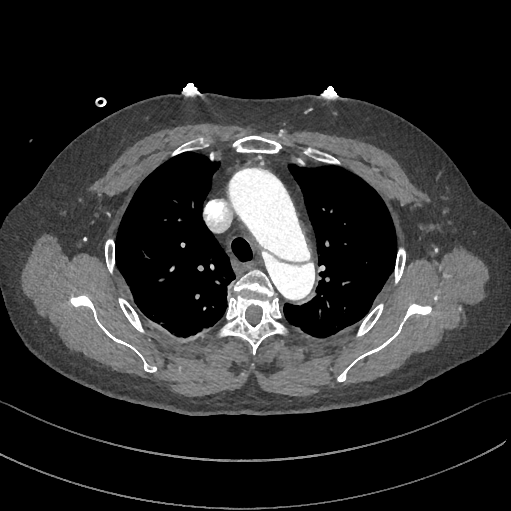

有些小伙伴开始着急了:鲁迅你别说了,我们家的CT分辨率低,平扫绝对看不出动脉夹层!

下图的胸部CT平扫,有什么致命的问题?

血管壁钙化啊,老年人很常见啊,能说明个锤子!

注意,看下面,钙化在血管的里面,不是在管壁!难道是血液钙化了?血液钙化?什么鬼?

这不是血液钙化,这是主动脉夹层导致的血管钙化内移!血液不会钙化,因为动脉夹层,导致钙化的内膜被压迫进入血管!

增强CT一看,就一清二楚了!